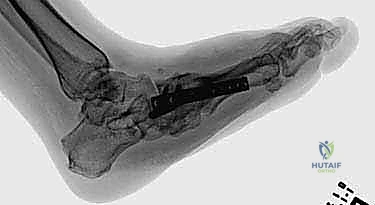

هذه هي المرحلة الأهم، حيث يتم دمج العظام المتضررة معاً لتكوين كتلة عظمية صلبة ومستقرة. يعتمد الدكتور هطيف على تقنيتين رئيسيتين حسب حالة المريض:

أ) التثبيت الداخلي الشديد (Superconstruct Internal Fixation):

استخدام صفائح معدنية سميكة جداً ومسامير طويلة (أقوى من تلك المستخدمة في الكسور العادية) لتثبيت العظام الهشة. يتم وضع هذه الدعامات داخل القدم لتكوين هيكل جديد.

ب) التثبيت الخارجي الحلقي (جهاز إليزروف - Ilizarov Apparatus):

يُعد الأستاذ الدكتور محمد هطيف من أبرز الخبراء في استخدام جهاز إليزروف في اليمن. يُستخدم هذا الجهاز عندما تكون جودة العظام سيئة جداً أو في حالة وجود التهاب أو قرحة مفتوحة تمنع وضع معادن داخلية. عبارة عن حلقات معدنية تحيط بالقدم والساق، متصلة بأسلاك دقيقة تخترق العظام، مما يوفر ثباتاً ميكانيكياً هائلاً ويسمح للمريض بالمشي التدريجي أثناء فترة الالتئام.